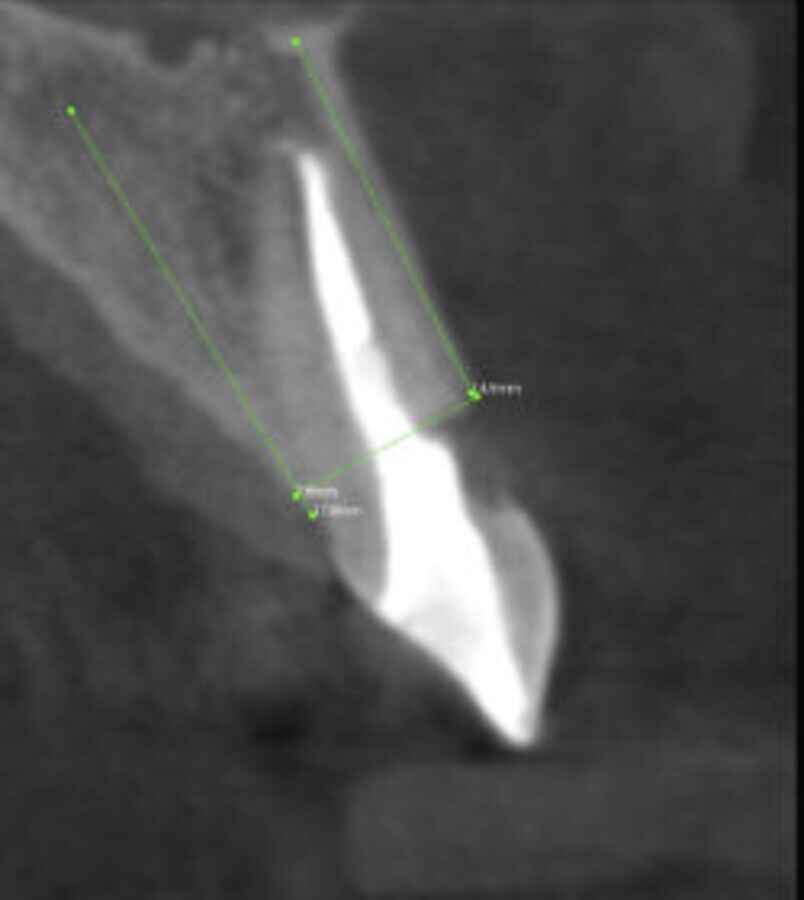

本文将逐步展示一单颗义齿美学修复案例。患者由于#11牙折前来就诊(图1)锥形束计算机断层扫描(CBCT)证实了牙折,并显示唇侧牙根有外部吸收(图2)。患牙必须拔掉,并决定在立即种植后进行临时的美学种植修复。计划采用短期的非包容式装载方式进行即刻种植体植入。

图2. CBCT:可见牙根断裂、唇面外吸收。